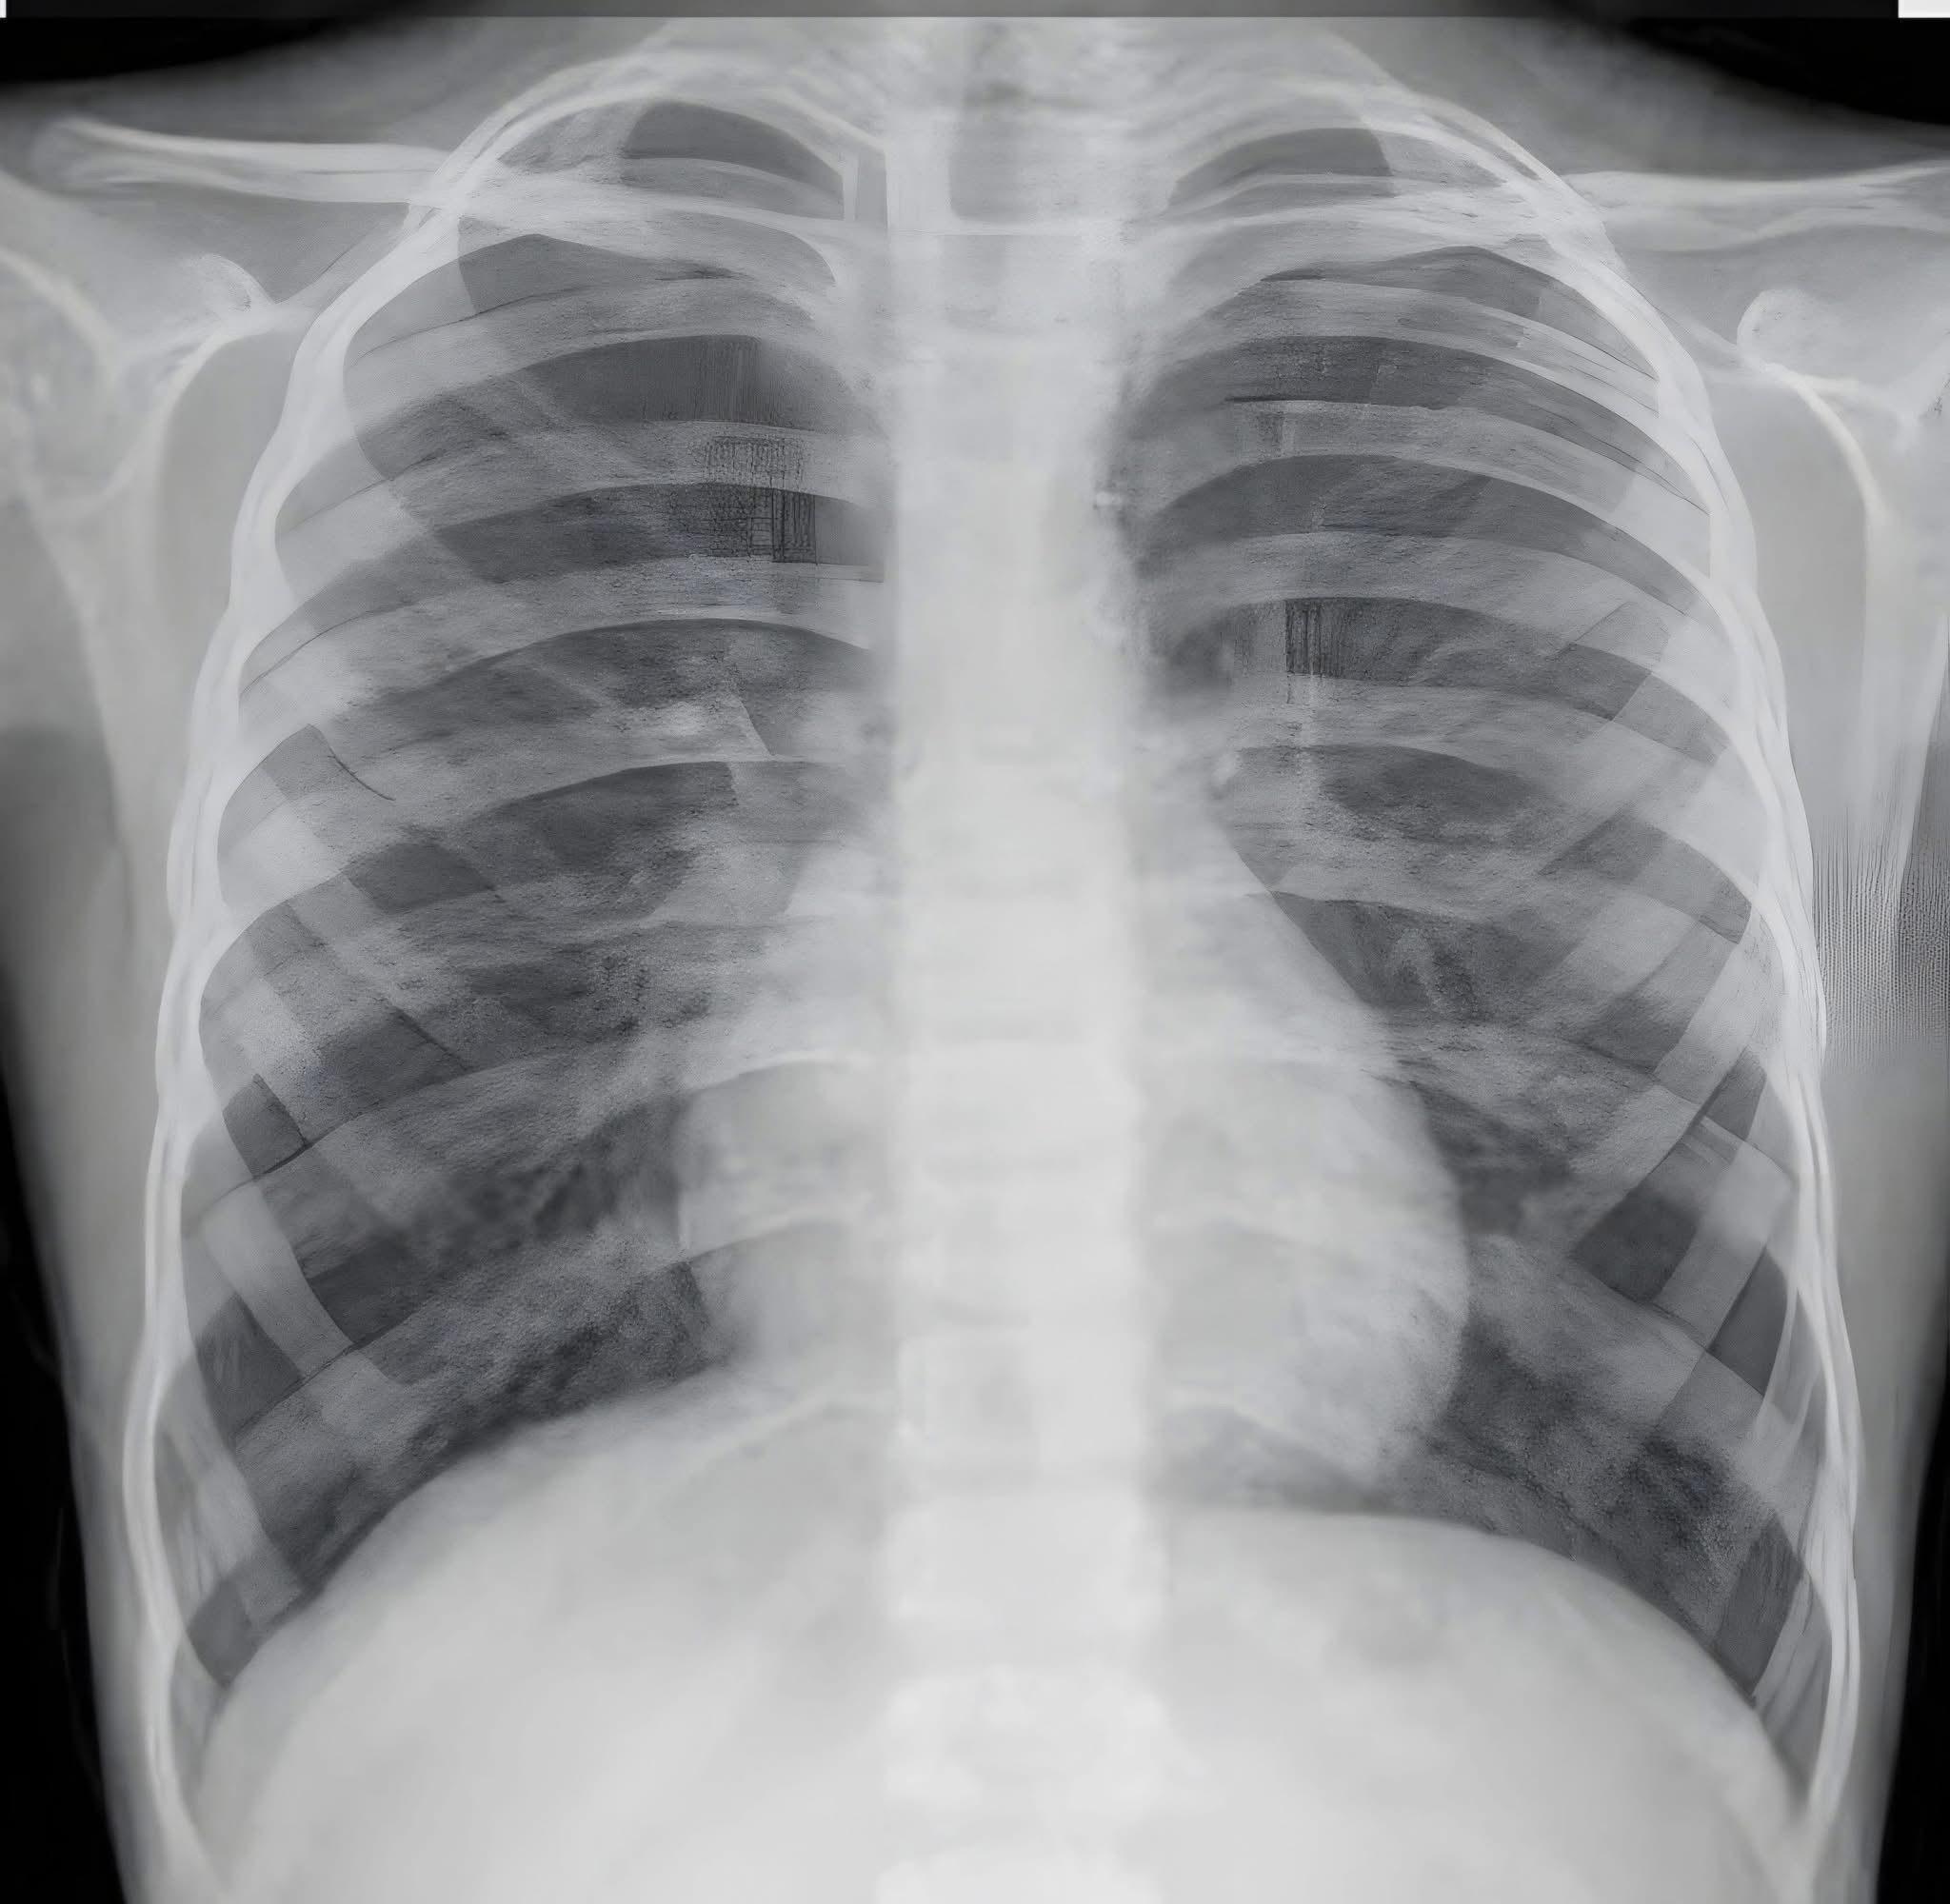

بعد تفاقم الأعراض، طلب طبيب الصدر إجراء أشعة مقطعية على الصدر، والتي أظهرت:

- احتقانًا في الرئتين.

- ارتشاحًا داخل الغشاء البللوري.

- تضخمًا ملحوظًا في حجم القلب.

وهنا كانت التوصية واضحة: ضرورة فحص القلب فورًا.